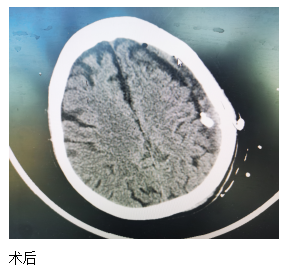

近日,一位84歲高齡患者來(lái)江寧中院就診,表現(xiàn)為:右側(cè)肢體的力量下降、不能獨(dú)立站立、言語(yǔ)不利、吐字不清。經(jīng)頭部CT檢查發(fā)現(xiàn),患者左側(cè)大面積慢性硬膜下血腫,嚴(yán)重壓迫腦組織。

患者收入院后,完善各項(xiàng)檢查,無(wú)明顯手術(shù)禁忌,中醫(yī)院神經(jīng)外科團(tuán)隊(duì)經(jīng)過精心周全的準(zhǔn)備,為其實(shí)施了腦膜中動(dòng)脈栓塞結(jié)合硬通道血腫穿刺引流的復(fù)合手術(shù)。術(shù)后第二天,患者肢體無(wú)力的癥狀得到了明顯改善,語(yǔ)言表達(dá)也恢復(fù)如初。患者及家屬對(duì)此治療效果非常滿意。